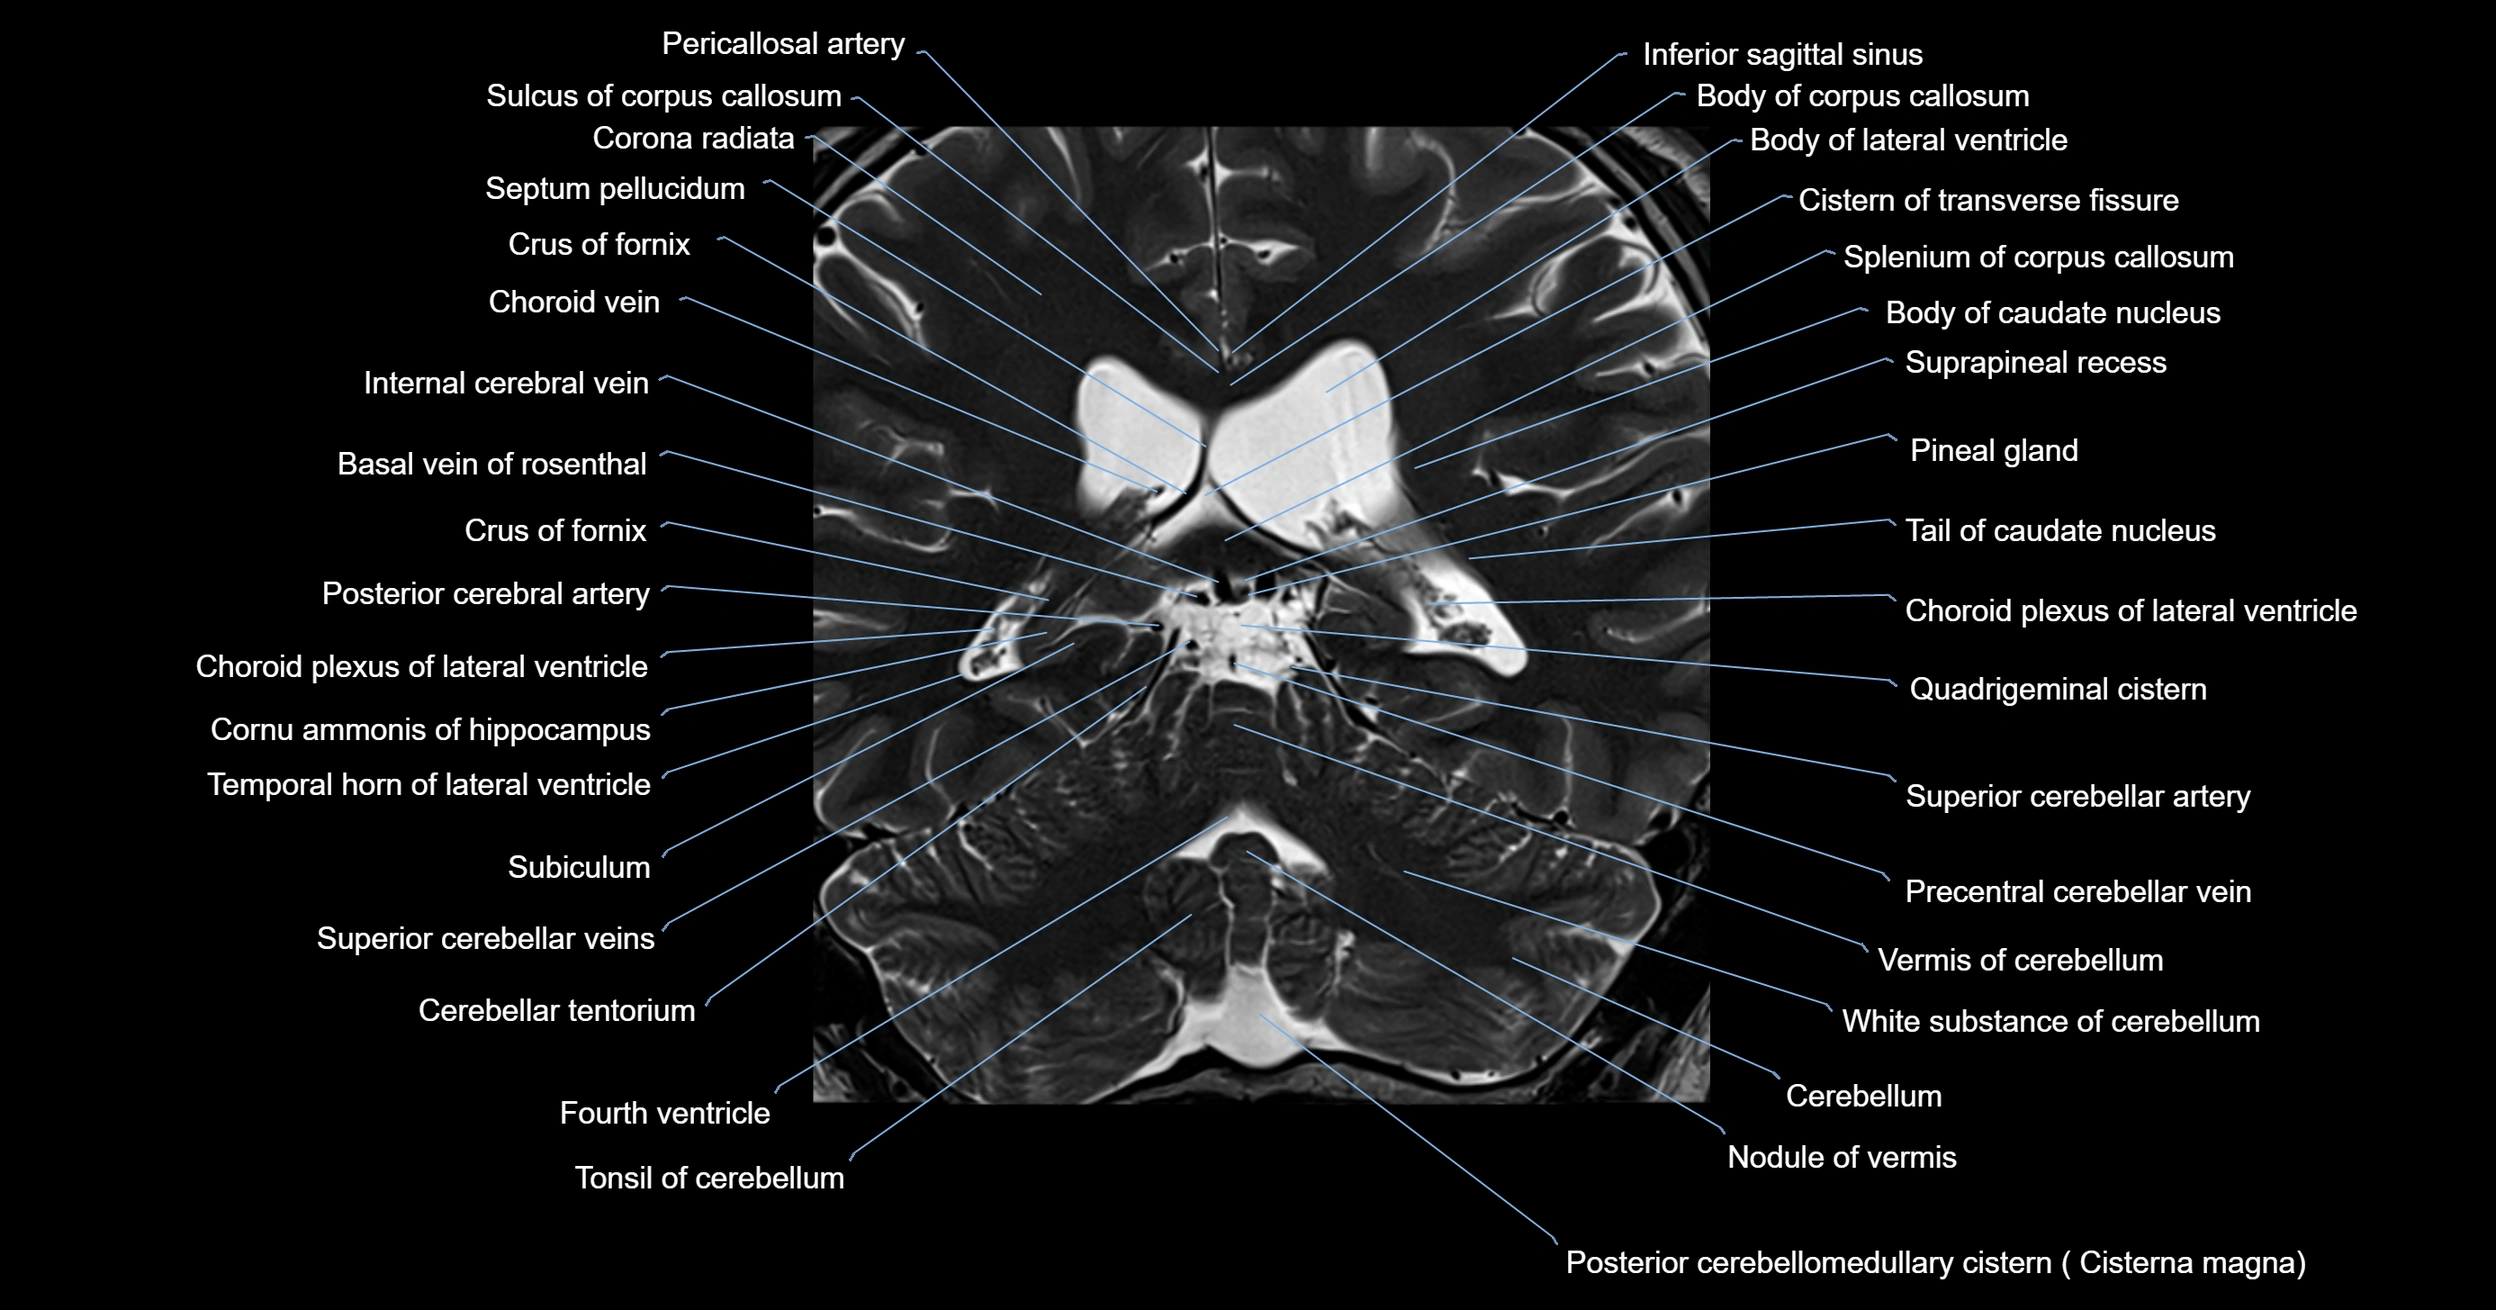

- Body of corpus callosum

- Body of lateral ventricle

- Cerebellum

- Choroid plexus of fourth ventricle

- Choroid plexus of the lateral ventricle

- Cistern of transverse fissure

- Cisterna magna

- Crus of fornix

- Internal cerebral vein

- Nodule of vermis

- Pineal gland

- Posterior cerebellomedullary cistern (cisterna magna)

- Posterior cerebral artery

- Precentral cerebellar vein

- Quadrigeminal cistern

- Splenium of corpus callosum

- Superior cerebellar artery

- Suprapineal recess

- Tail of caudate nucleus

- Tonsil of cerebellum

- Vermis of cerebellum

- White substance of cerebellum